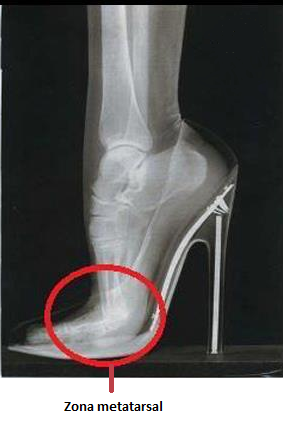

Hay estudios realizados sobre la distribución de las cargas en el pie cuando utilizamos un tacón y dichas investigaciones concluyen en que la carga en la parte del antepie se ve muy aumentada y por el contrario disminuido en el talón, es decir, apoyamos casi todo nuestro peso en la zona de los metatarsianos (véase la imagen de abajo).

Además, el tacón es una superficie inclinada que por inercia hace que los dedos se desplacen hacia delante, provocando así problemas en ellos, ya sean rozaduras, ampollas o deformidades tales como dedos en garra, aparición de “hallux valgus” (conocido como juanete), seguido de un amplio abanico de problemas [6].

Otra investigación concluyó que ocho de cada diez mujeres estadounidenses se quejan de enfermedades en los pies causadas por el calzado. Con tacones bajos, el peso del cuerpo se distribuye más adecuadamente; al caminar con tacones altos, 75% del cuerpo descansa en los metatarsos, y también se atribuye al uso de calzado de tacón que 70% de las mujeres padezca envejecimiento prematuro de los discos de la columna [7].

- Pie:

En principio provoca una sobrecarga en la parte del antepie (zona metatarsal), ya que al ser un plano inclinado el peso del cuerpo se desplaza hacia delante dañando la parte de los metatarsianos y predispone a sufrir “hallux valgus” (conocido popularmente como juanete) y “hallux rigidus” (rigidez en el dedo). A parte de estas consecuencias, normalmente el calzado de tacón suele ser estrecho, con lo que se pueden producir deformidades en los dedos, como por ejemplo, los dedos en garra, entre otros. Además de complicaciones en la piel como callosidades o durezas como consecuencia de un aumento de presión en la misma zona. - Tobillo: